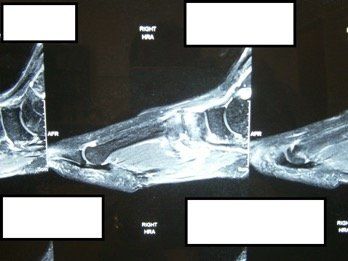

Midfoot arthritis refers to arthritis in the middle part of the foot. There are a number of joints that make up this part of the foot and arthritis in this area presents with degenerative changes. Degenerative changes are depicted by pain in the area, instability of the joint, narrowing of the joint space, osteophytes or bone spurs, cystic areas within the bone, damage to the joint cartilage, and laying down of extra bone.

Surgery for midfoot arthritis ranges from simple to more complex procedures. Surgery may involve a “clean-up” of the joint by removing damaged cartilage and bone spurs, resection of a part of the joint, fusion (stiffening) of one or more joints. Medical imaging, such as x-rays and MRIs are usually obtained prior to surgery to determine the extent of the injury and to plan for the proposed surgery.